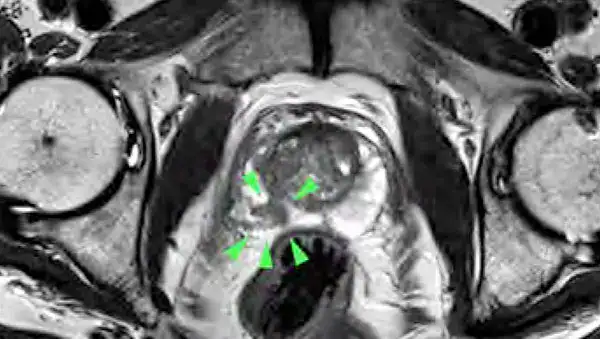

Prostatakrebs ist bei Männern der häufigste bösartige Tumor. Doch die Früherkennung macht große Fortschritte: In der Radiologie Darmstadt steht ein Hochfeld-MRT, mit dem selbst kleine Karzinome festgestellt und unklare Befunde geklärt werden können.

Dr. Dick: Die bisherige Diagnostik weist Lücken auf: So kann der PSA-Wert auch bei nicht-bösartigen Prostata-Vergrößerungen erhöht sein. Und die Abtastung der Prostata ist weder angenehm noch genau. Beim transrektalen Ultraschall über den Mastdarm werden Tumore häufig nicht erfasst und auch die sonographisch gesteuerte Biopsie weist diagnostische Schwächen auf. Deshalb hat die urologische Gesellschaft die multiparametrische Magnetresonanztomografie (mpMRT) in die Leitlinie mit aufgenommen. Diese MRT-Methode ist genau und schonender für den Patienten, auch muss ihm bei 3 Tesla- Geräten keine Spule mehr in den Enddarm eingeführt werden. Neben der Messung anatomischer Werte werden bei diesem speziellen MRT auch die Zelldichte gemessen und die Gewebedurchblutung nach der Gabe von Kontrastmitteln durchgeführt, wodurch wir eine sehr gute Diagnostik haben. Die Datensätze können dann mit den Ergebnissen der Ultraschalluntersuchung verglichen werden. Anschließend kann – wenn nötig – eine gezielte Gewebeprobe entnommen werden.

Mit dem Hochfeld MRT mit 3 Tesla von Siemens steht der Radiologie Darmstadt die neueste Technik – ein hochmodernes Gerät für die mpMRT zur Verfügung – nicht-invasiv und treffsicherer als die ungesteuerte Biopsie. Durch die Kombination räumlich hochauflösender Bilder mit Zelldichtemessungen können wir selbst kleinste Tumore unter 1 cm zuverlässig detektieren. Außerdem können wir entscheiden, ob es sich um einen gutoder bösartigen Tumor oder um eine Entzündung handelt. Die Datensätze können dann mit den Ergebnissen der Ultraschalluntersuchung verglichen und gezielt die richtige weitere Vorgehensweise geplant werden. Neben dem hochmodernen MRT-Gerät verfügen wir als einziger Standort in Südhessen über eine spezielle Software zur Auswertung nach neuesten Richtlinien. Die Auswertung der Daten stellt besondere Anforderungen an den Befunder. Als Praxis sind wir über den BDR (Bund Deutscher Radiologen) zertifiziert, und persönlich bin ich von der Arbeitsgemeinschaft Uroradiologie der Deutschen Röntgengesellschaft mit der Qualitätsstufe Q1 für die mpMRT zertifiziert.